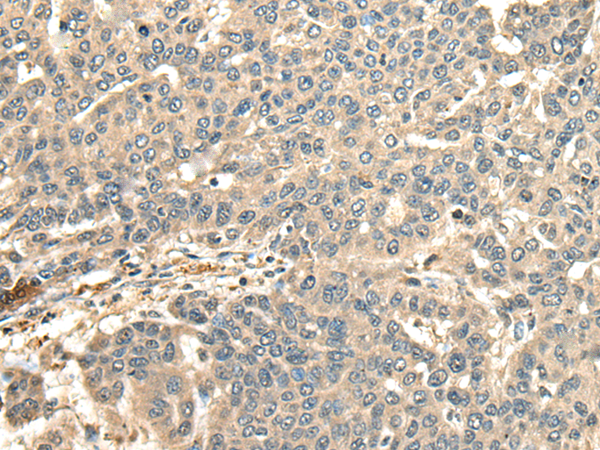

分类: 科研抗体货号: P09446别名:应用: IHC反应种属: Human, Mouse

分类: 科研抗体货号: P09445别名: HSPC065应用: IHC反应种属: Human, Mouse

分类: 科研抗体货号: P09464别名: CEP2; BORG1应用: IHC反应种属: Human, Mouse, Rat

分类: 科研抗体货号: P09463别名: CDC45L; MGORS7; CDC45L2; PORC-PI-1应用: IHC反应种属: Human, Mouse